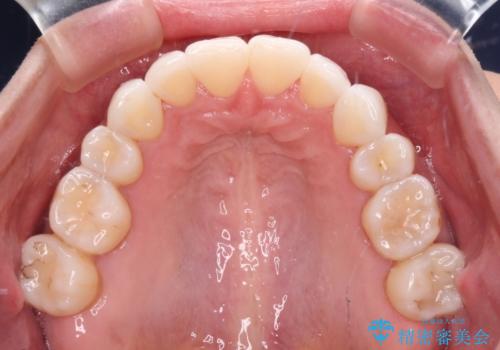

- 上の前歯の出っ歯を治したいとのことで来院された患者様です。

後戻りによる再矯正というもともあり、インビザラインを希望されていました。

上顎の歯は後方移動とIPR(歯と歯の間を削る)によって口元が引っ込むように、下顎は歯列全体の拡大とIPRによって上顎とバランスよく咬み合うように設計し、インビザラインにより治療を行うこととしました。